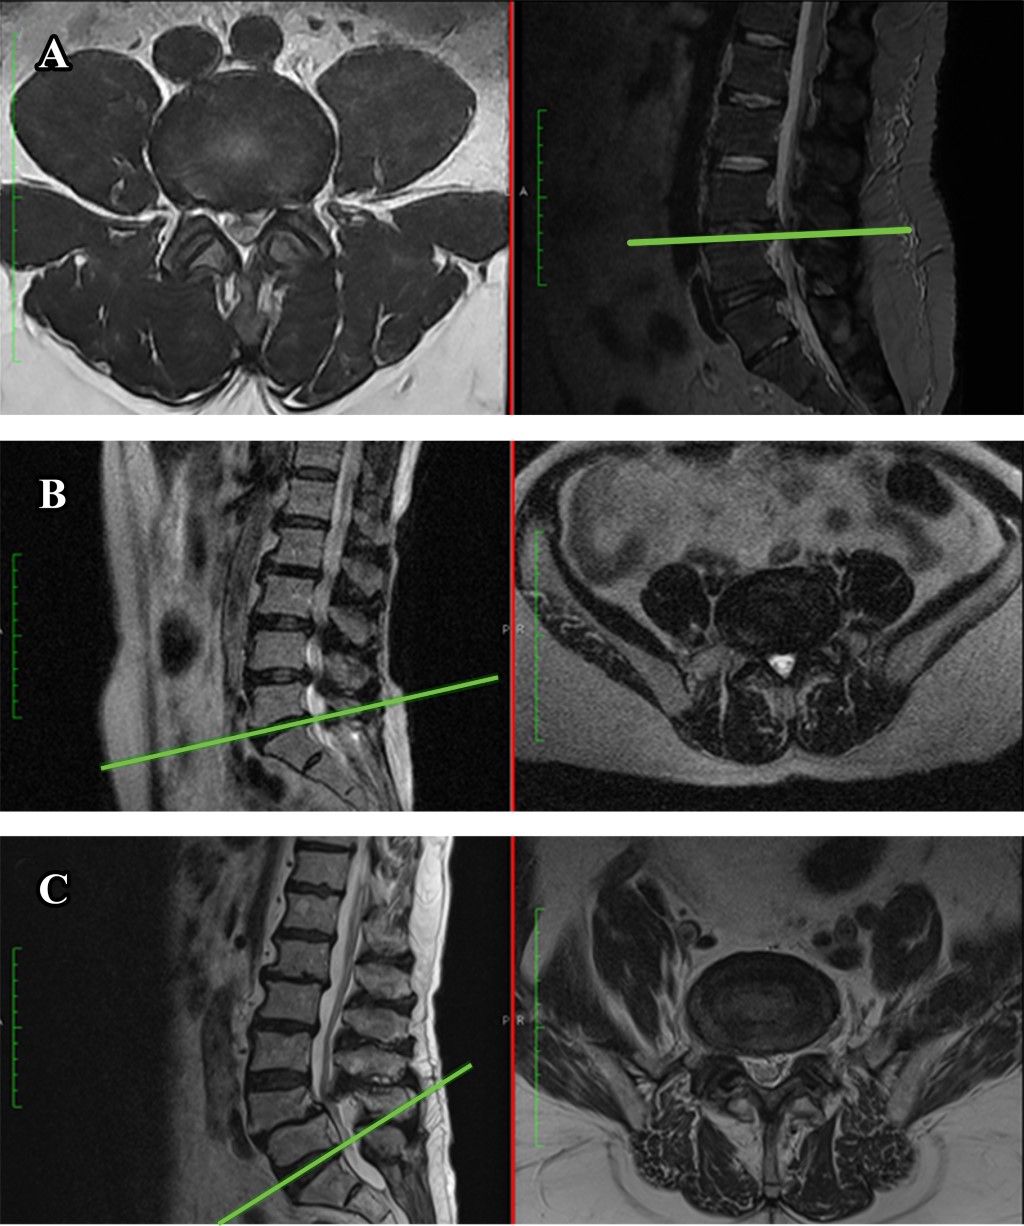

La enfermedad lumbar degenerativa (ELD) puede comprenderse como un espectro de cambios patológicos que abarcan desde la degeneración discal, la hernia discal, la espondilolistesis y la estenosis espinal lumbar o conducto lumbar estrecho. A lo largo del envejecimiento, al que se suman alteraciones biomecánicas, la columna sufre adaptaciones que fueron descritas por Kirkaldy-Willis & Farfan, se les divide en una secuencia de tres etapas progresivas: una fase de disfunción temporal, la fase de inestabilidad y, por último, una fase de estabilización o anquilosis.1 Estos cambios en los tejidos musculo esqueléticos se acompañan de dolor. En conjunto, esta entidad condiciona una reducción en la calidad de vida. De acuerdo con el estudio Global Burden of Disease que estudia el impacto económico en relación con los años de incapacidad laboral, condicionó 83 millones de años ajustados a incapacidad tan solo en 2010. Actualmente se estiman en el mundo 266 millones de individuos con enfermedad discal degenerativa y 103 millones con conducto lumbar estrecho diagnosticados al año.2 El dolor asociado a la ELD es multifactorial. Algunas fuentes anatómicas conocidas incluyen: los discos intervertebrales, las articulaciones cigapofisarias, el hueso y periostio, los músculos, tendones y ligamentos; así como la raíz nerviosa, el ganglio dorsal, la duramadre y algunos vasos. Se estima que hasta 80% de la población tendrá al menos un episodio de dolor lumbar en su vida,3 del que los espasmos o contracturas musculares son una de las causas más frecuentes. Para un abordaje integral, la comprensión de los cambios que sufre la musculatura paraespinal a lo largo del ciclo de vida y las adaptaciones a las que es sometida contribuye en la determinación de la severidad del proceso degenerativo al momento de la evaluación del paciente y para sugerir las mejores intervenciones médicas y quirúrgicas para el tratamiento de dolor. La relación que guarda la degeneración muscular y la ELD ya ha sido estudiada en múltiples trabajos de entre los que destaca la serie realizada por Kjaer y colaboradores en la población danesa. En ella, además de demostrar la asociación entre la degeneración muscular y el dolor de espalda baja en adultos, propuso una metodología simple para el especialista en columna al momento de medir la severidad de la infiltración grasa del multifidus spinae, a través del análisis de la imagen por resonancia magnética (IRM) y la clasificación en tres grupos (Figura 1).4 Otra serie destacable es la de Hildebrandt y asociados quienes determinaron que la severidad de infiltración grasa se relaciona también con disfunción lumbar, principalmente en el rango de movimiento.5 La participación de la degeneración muscular ha sido estudiada más recientemente en el segmento espinal cervical, estableciéndose una relación estrecha entre mayor infiltración grasa y puntajes más altos en la escala de discapacidad de Nurick y de la Asociación Japonesa de Ortopedia en su versión modificada (mJOA) en pacientes mielopáticos.6

Pacientes. Se incluyeron pacientes con alguno de los siguientes diagnósticos de primera vez realizados en nuestro centro: hernia discal, conducto lumbar estrecho o conducto lumbar estrecho con escoliosis degenerativa. Los expedientes fueron capturados de forma prospectiva desde Enero de 2021 en la consulta externa del servicio de cirugía de columna de un hospital de tercer nivel, centro de referencia de siete estados del interior de la república en las zonas Bajío y Occidente. Se excluyeron pacientes que no contaran con imagen por resonancia magnética (IRM) y radiografías dinámicas (lumbosacra en flexión y extensión) en sistema, así como aquellos con una historia clínica incompleta. Todos los pacientes fueron clasificados de acuerdo con la escala visual de Kjaer para infiltración grasa paraespinal en alguno de los tres grupos descritos (Figura 2). Las variables a evaluar se agruparon en clínicas y radiográficas. En el primer grupo se incluyen: edad, tabaquismo, obesidad, presencia de dolor tipo axial, temporalidad del dolor, severidad expresada con escala visual análoga (EVA). Las variables radiográficas incluidas son: número de segmento enfermos, segmentos involucrados, diagnóstico por imagen y presencia de espondilolistesis.